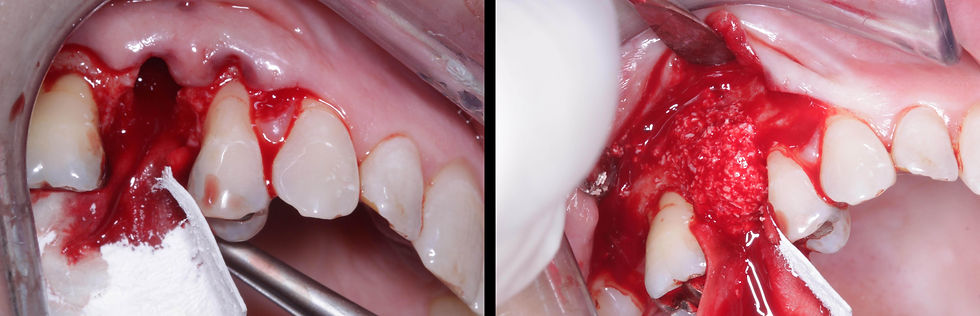

Bone regeneration: the alveolus is filled with deproteinized bovine bone particles covered with a resorbable collagen membrane.

Tension-free secondary wound closure with PTFE sutures. Sutures are removed after 2 weeks